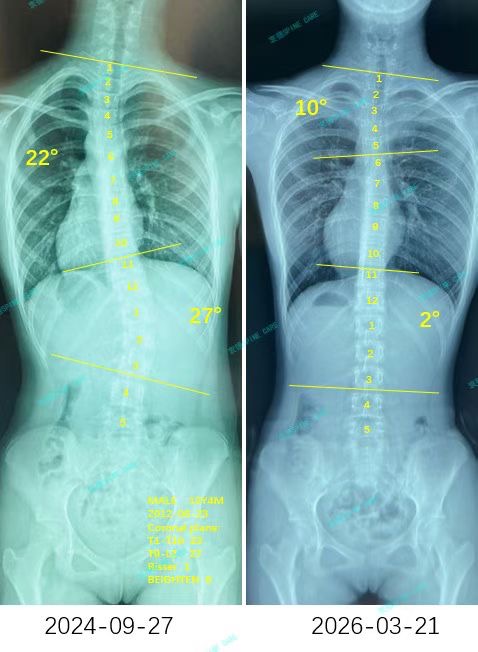

来自家长对衷德的评价(童童妈妈)

衷德脊柱,我们只关注侧弯保守治疗~